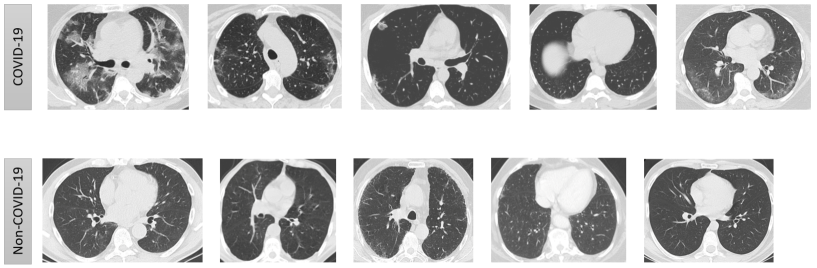

Thoracic radiology evaluations found high rates of ground-glass opacities and consolidations in COVID-19 patients. One can observe the ground-glass opacities (GGOs) together with consolidations in the CT-Scan of COVID-19 images. These regions are isolated with difference in shapes (left image in Fig. 8), which is captured by PDs associated to and . Moreover, these regions have unique shape in the intensity plot, see appearance of alps, saddle points in Fig. 8 (right image). These are recorded by PDs of Lower-star-filtration and .

3.1.2 PDs: Capturing the Visible

This filtered complex, defined in the previous section, is able to capture the key features of a CT-scan, like, peaks, variations in intensity, etc. Connected components and appearance of loops at different intensity levels are captured in the PD’s of , and respectively (see Fig. 10). The PDs of and for the images in Fig. 10 are given in Fig. 12. It is evident that the difference in their visual appearance is captured by these PDs.